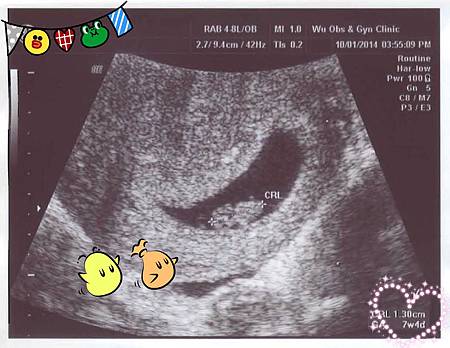

「7w4d」哈囉!看見你了!

No.2 還在我的肚子裡

稱不上是第一次見面,只能說"我看到你囉!"

雖然一開始有一點小小的不穩定

從驗到孕就開始持續嗜睡,躺平後就秒睡,

持續了兩個多星期,突然間不嗜睡了,卻又開始擔心No.2是不是沒事

雖然不是第一次當媽了

但是感動卻比第一次當媽還要多得多!

這次聽見噗通噗通的心跳時

竟然感動到想哭!

No.2 要繼續乖乖長大

我們一家四口一起幸福吧❤